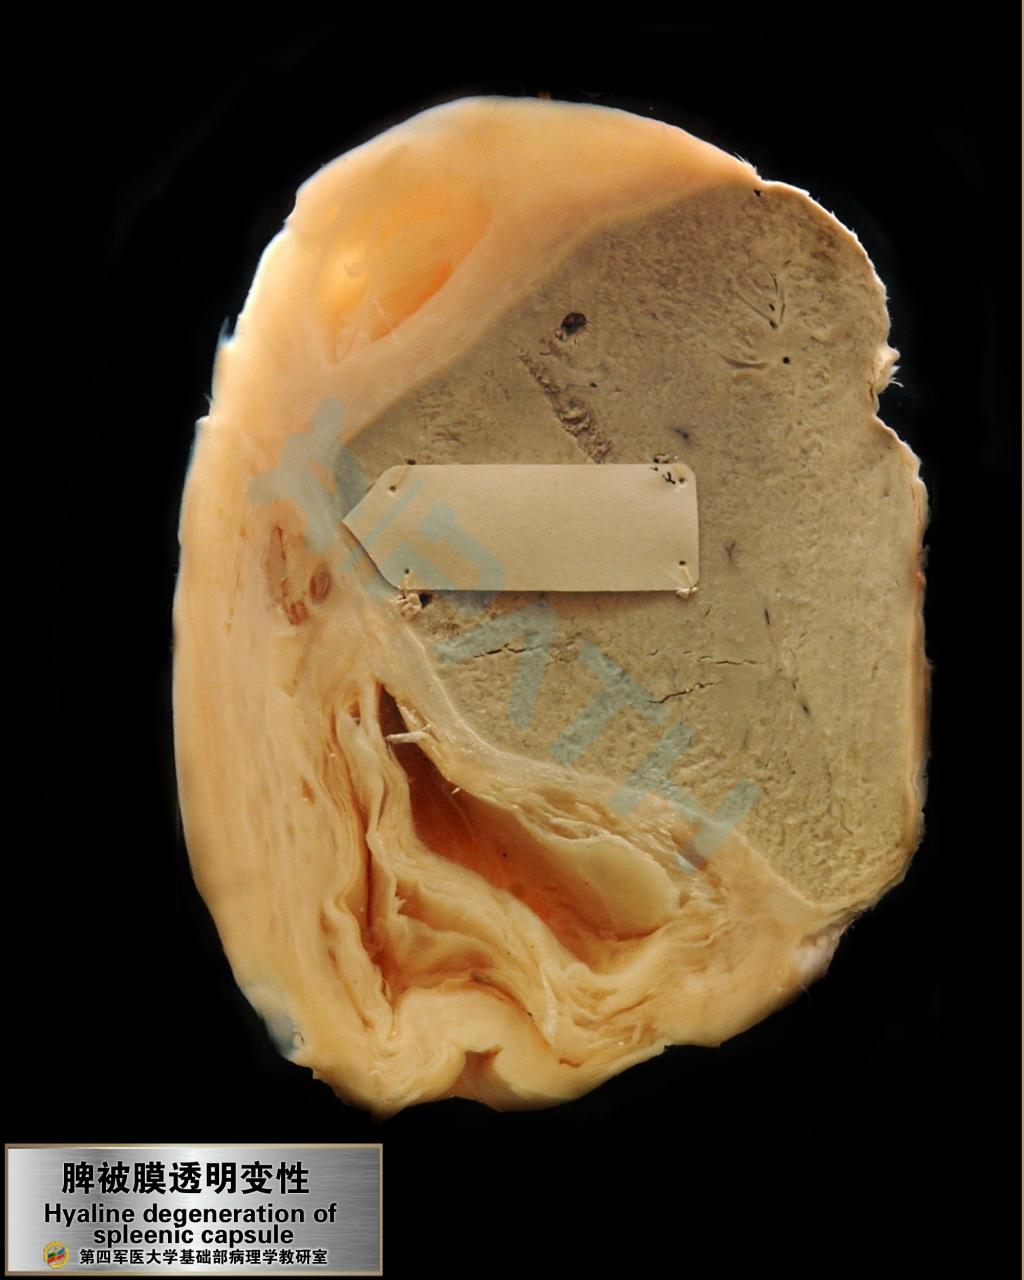

脾脏-脾被膜透明变性